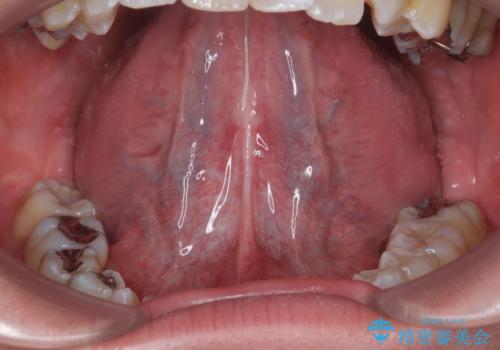

舌小帯が気になる。 舌小帯切除術

- 滑舌が気になるため舌小帯を切りたいとのことで来院された患者様です。

舌小帯切除を行い、滑舌の改善をはかります。

治癒も良好で、しゃべりやすくなったと大変喜んでいただけました。